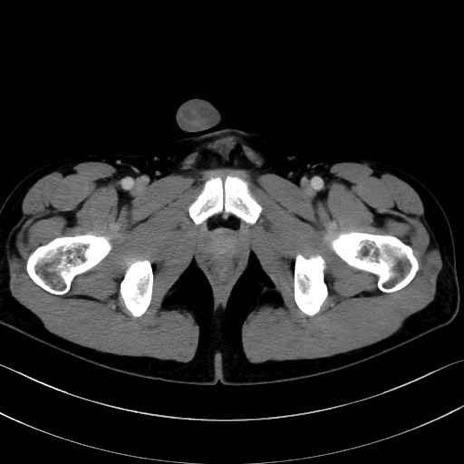

精嚢(seminal vesicle)のCT画像における解剖

症例

【症例】20歳代 男性 スクリーニング